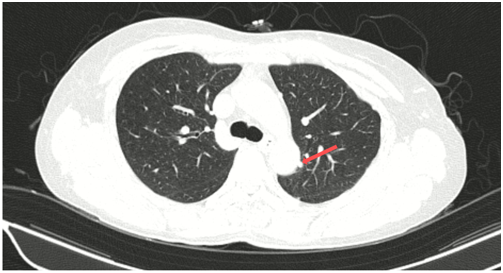

CT ngực (05/2024):

Hình 2: Hình ảnh tốt đặc ở phân thùy S6 phổi trái, đường kính 17 mm, bờ tua gai. Không thấy hạch trung thất to.